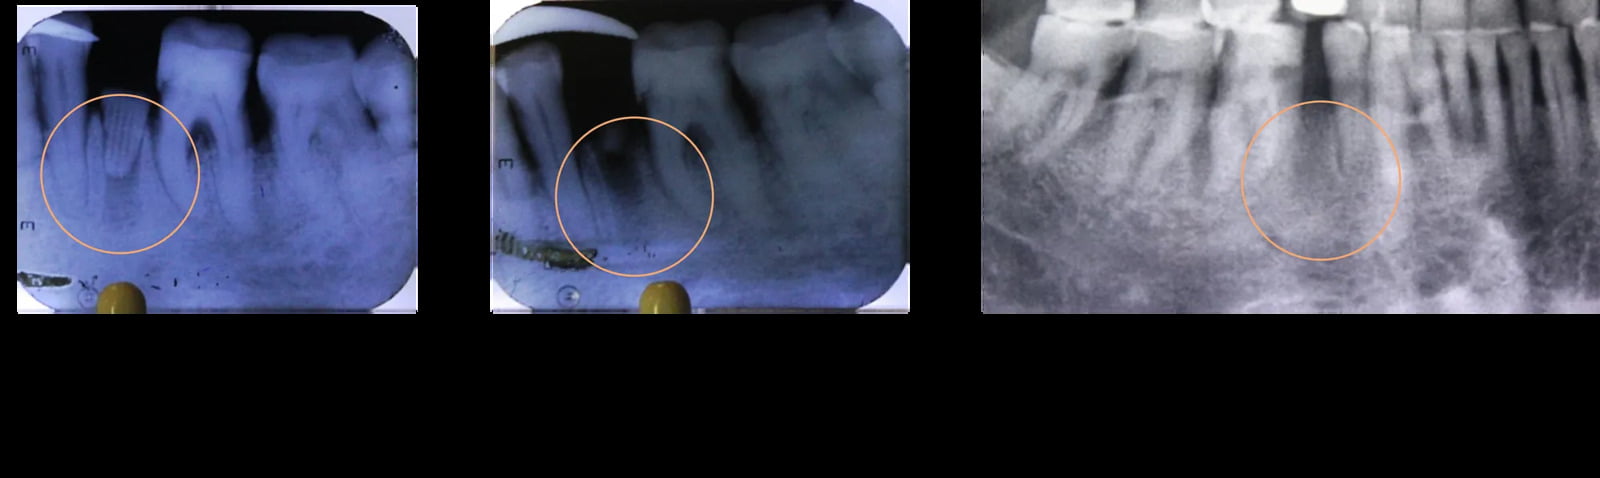

Note: The above clinical studies on reconstruction and bone regeneration of critical-sized bone defects particularly around those defects in the 1–3.5 cm range have demonstrated good clinical and patient outcomes.